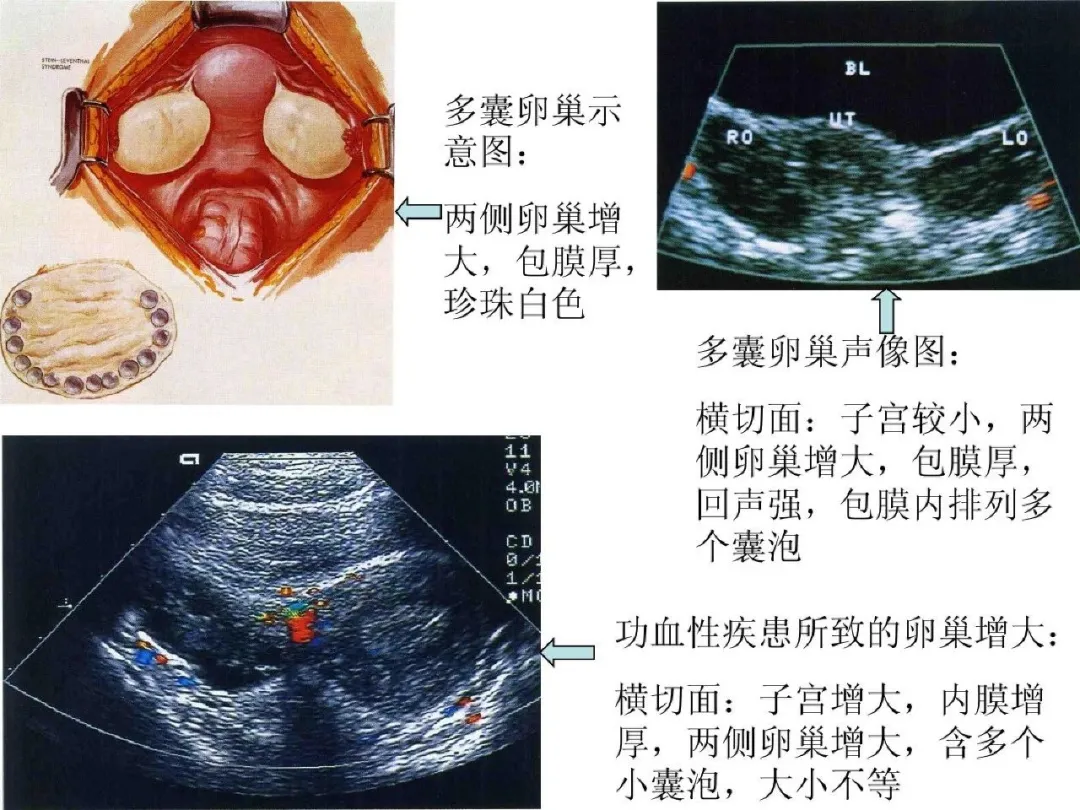

●多囊卵巢:双侧卵巢均匀增大,形态规整;壁厚光滑,回声增强;显示卵巢内有10多个甚至数十个直径<10mm的囊泡,边界清晰;子宫较小;卵巢动脉血流阻力升高。